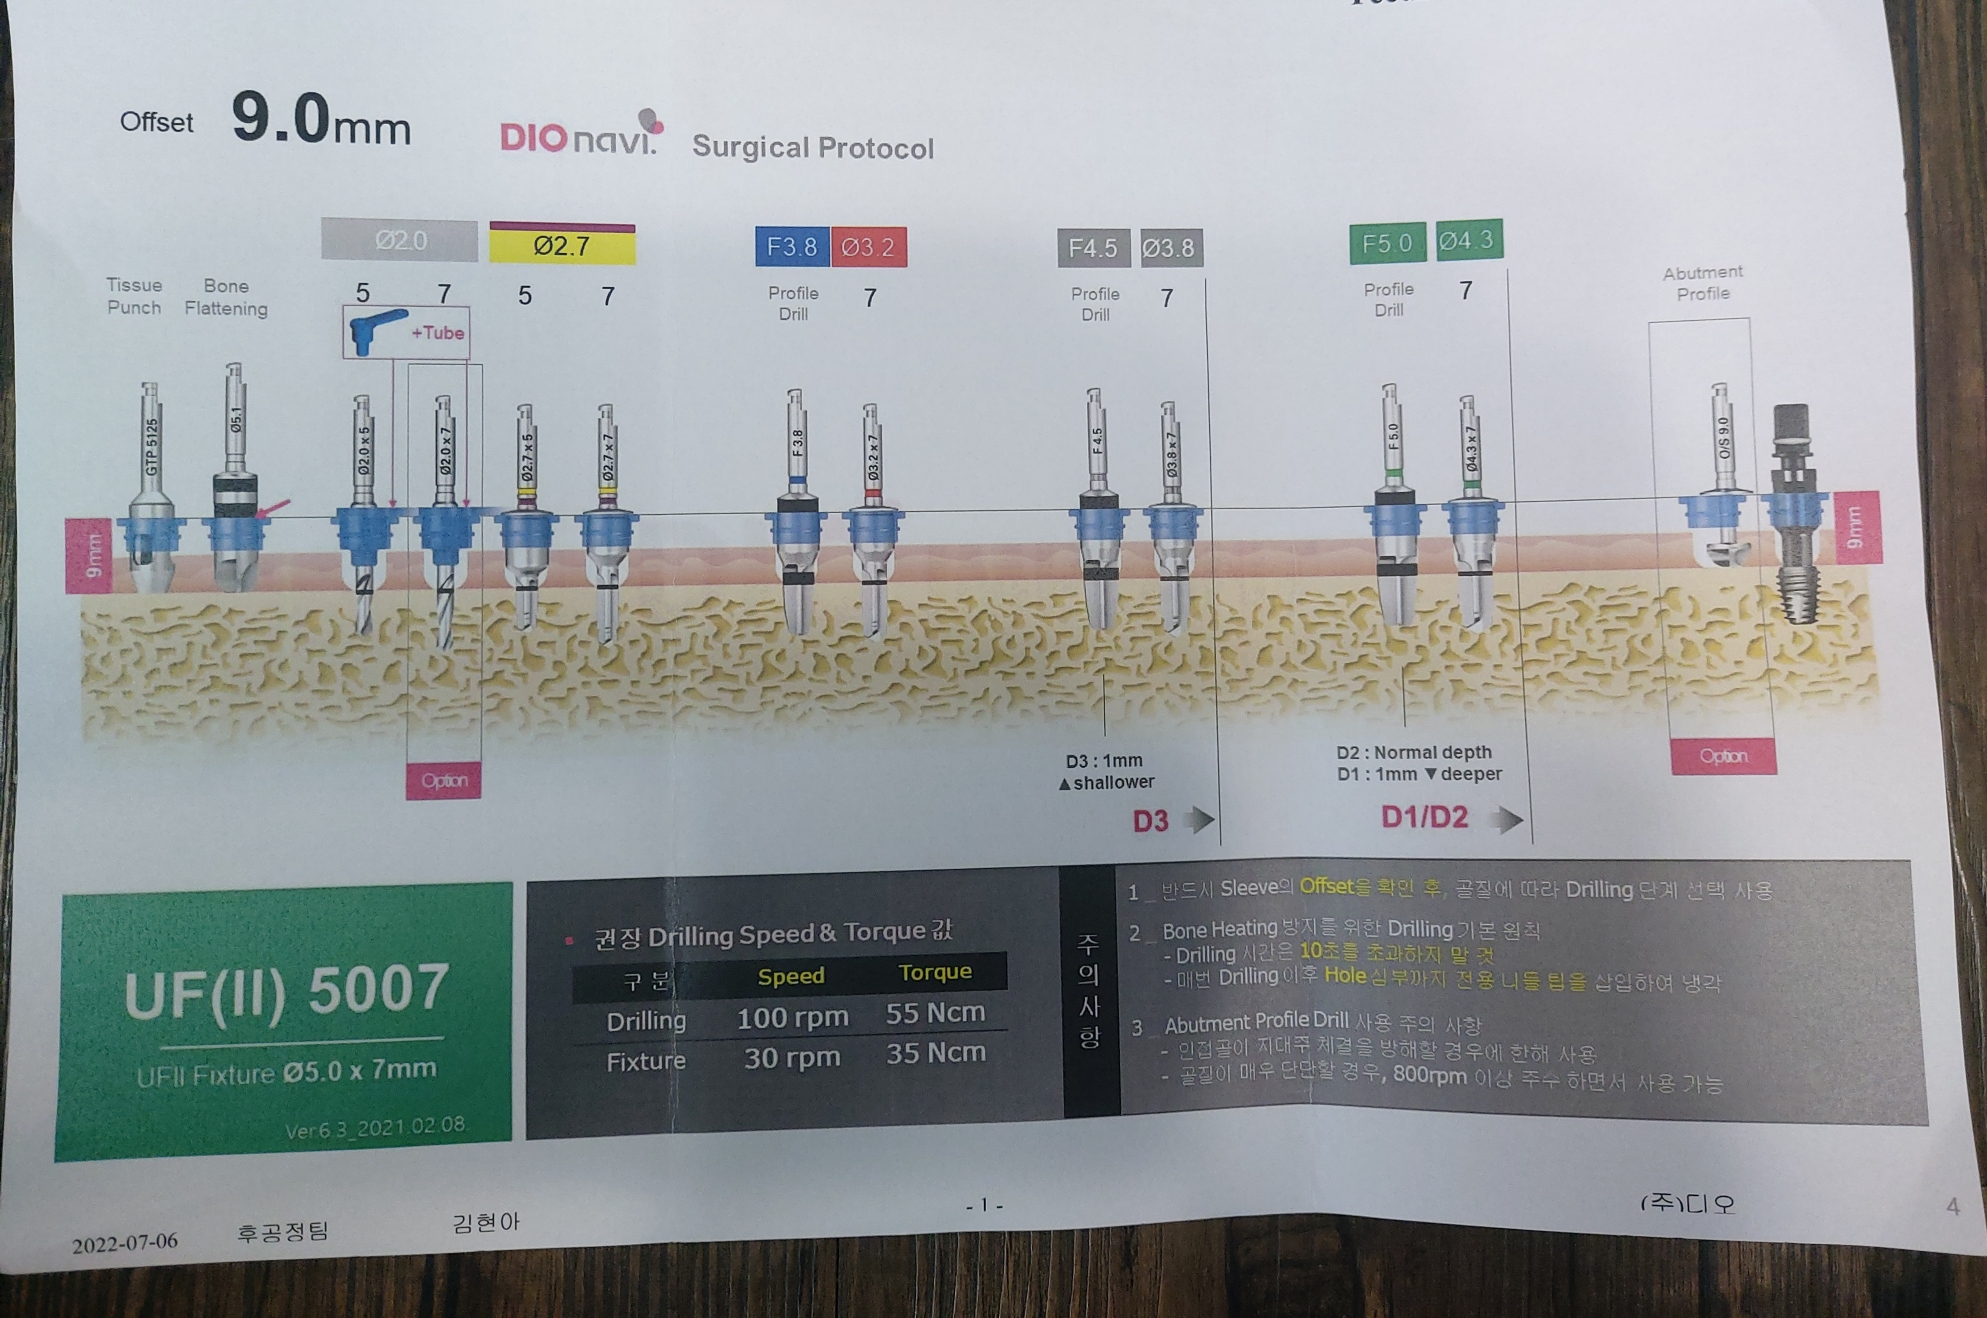

수술전 씨티와 구강스캐너를 이용하여

미리 모의 수술을 진행한 스텐트를 가지고 임플란트를 식립하는 네비게이션 임플란트 입니다.

또한 수술시 3차원적으로 계획된 스텐트를 가지고

아직 네비게이션 수술에 많은 경험이 없기에

최대한 스터디를 준비해서 진행했구요.

실제 수술이다 생각하고

실제 수술 킷트로 수차례 모의 수술을 진행하였습니다.

모의 수술중 의문 사항은 디오 임플란트 본사 담당자와 원활히 소통 하였고